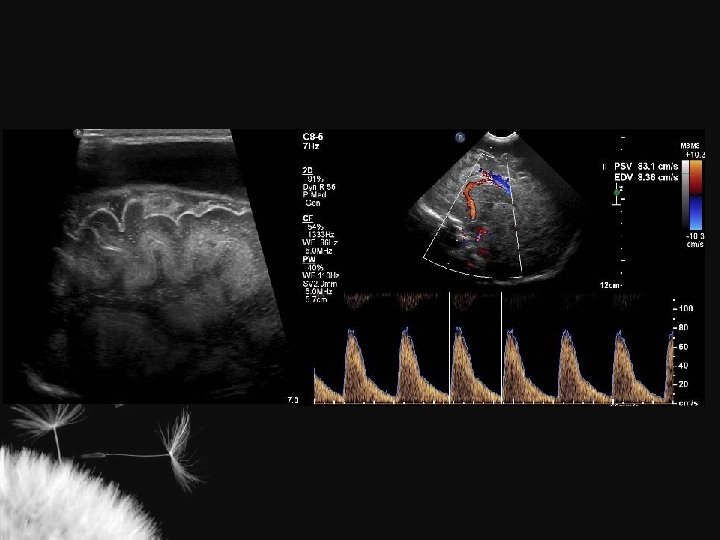

SISTEMA VENOSO

Velocidades do fluxo venoso em RN termo Vaso Velocidade média (cm/sec) Veias terminais 3, 0 + 0, 3 Veia cerebral interna 3, 3 + 0, 3 Veia de Galeno 4, 3 + 0, 7 Seio reto 5, 9 + 1, 0 Seio sagital superior 9, 2 + 1, 1 Seio sagital inferior 3, 5 + 0, 3 Taylor GA. Radiology 1992; 183: 449 -52

LESÃO HIPÓXICO-ISQUÊMICA NO RN TERMO